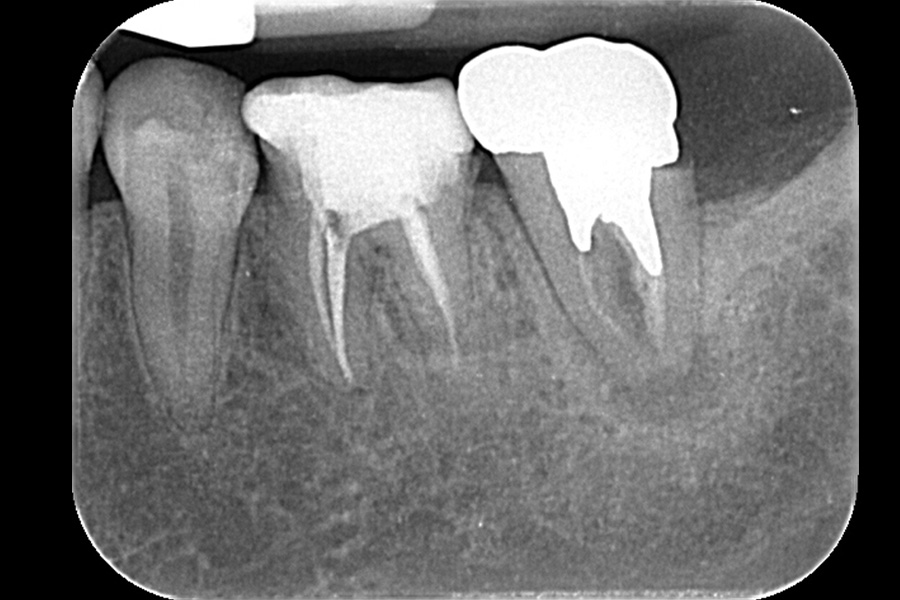

治療前

| 主訴 | 左下の奥歯が腫れている |

| 治療内容 | 下顎左側第二大臼歯 再根管治療 |